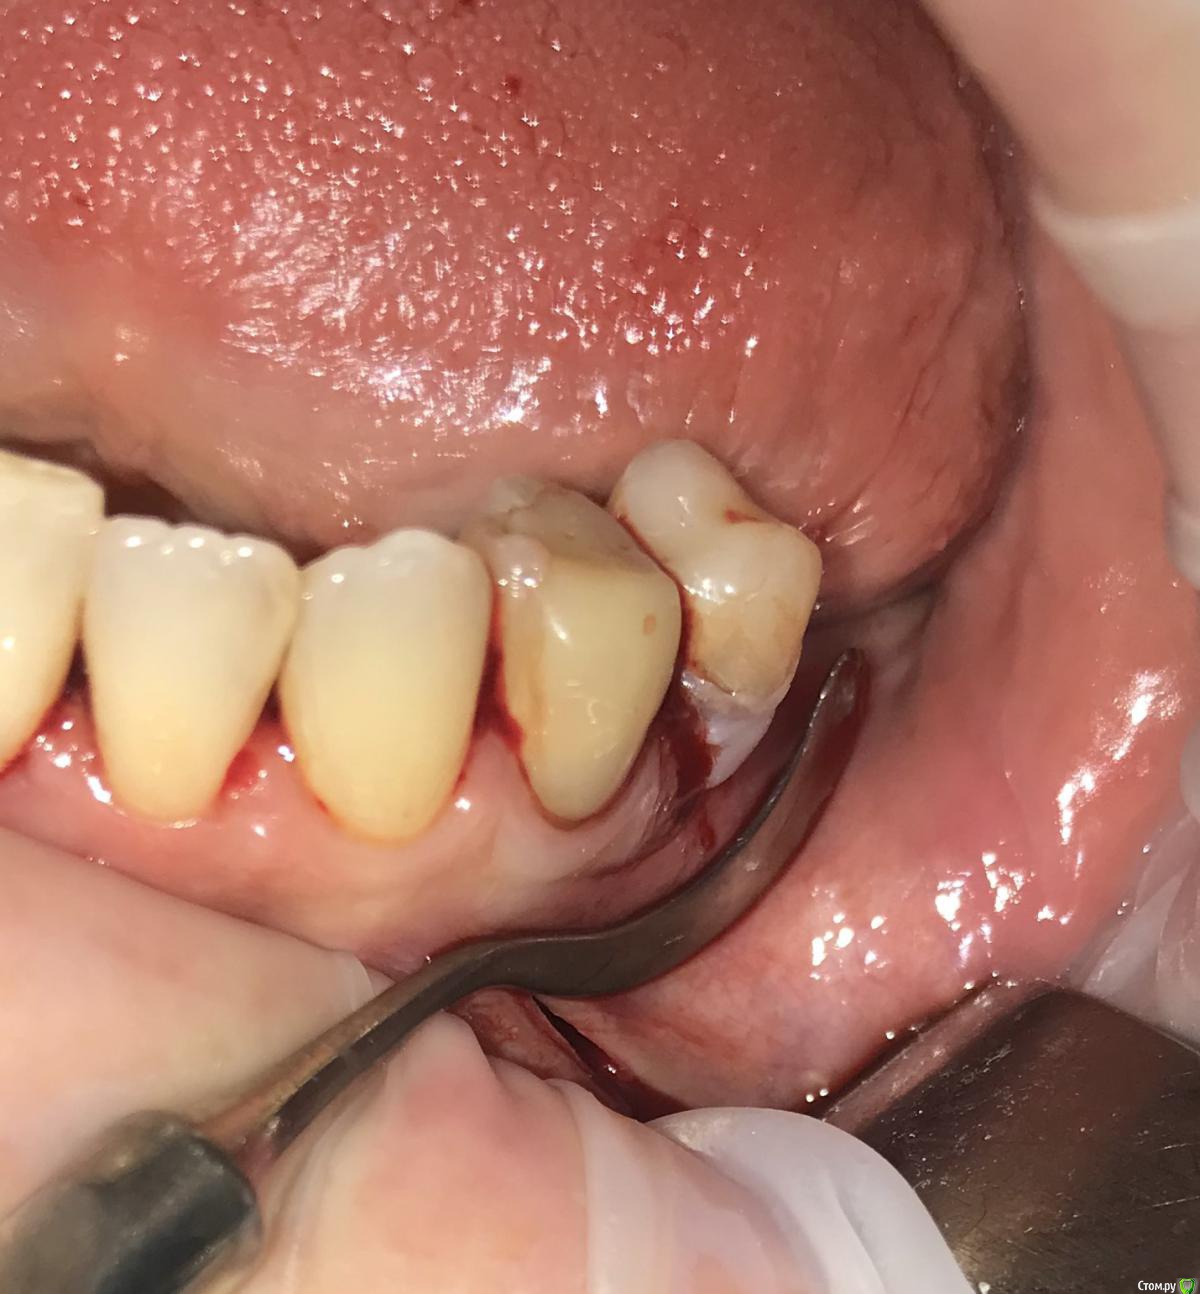

колесников Опубликовано 27 сентября, 2019 Автор Поделиться Опубликовано 27 сентября, 2019 Улучшение объема и качества мягких тканей в пришеечной области у ранее поставленных имплантов ,посредством тоннельной костной пластики. Объём 0,5г. Вид через 6 мес. 3 Ссылка на комментарий